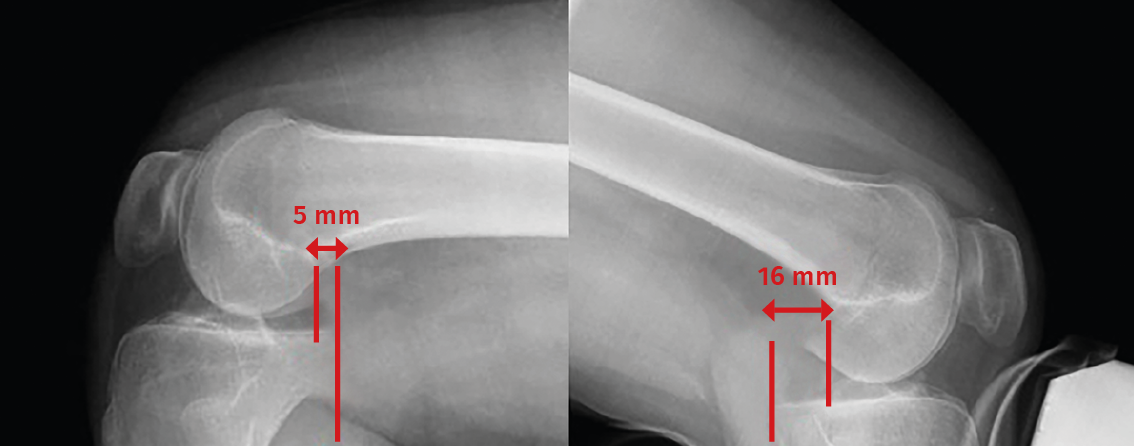

• Posterior drawer test. This is done with the patient in supine decubitus and the knee in 90° flexion. The test involves the application of pressure in a posterior direction of the proximal region of the tibia, observing posterior tibial translation in the injured knee with respect to the contralateral knee (Figure 2). A posterior displacement of the tibia of 0-5 mm is considered to correspond to a grade I lesion, 6-10 mm to a grade II lesion and >10 mm to a grade III lesion. Assessment of the degree of displacement is subjective, and thus implies important interobserver variability. If the tibial plateau remains located anterior to the medial femoral condyle, the lesion is considered to correspond to grade I, while if it is located at the same level as the femoral condyle the lesion corresponds to grade II, and if the plateau extends beyond the medial femoral condyle, the lesion corresponds to grade III (Figure 2)(10,11).

Figure 2. Initial position of the tibia reduced in the posterior drawer manoeuvre (A) compared with posterior tibial translation without reduction (B).

Posterior translation of the tibia is measured as the minimum distance between a line tangential to the posterior cortical layer of the tibia and another line tangential to the posterior margin of the femoral condyle at the most dorsal point of the Blumensaat line (Figure 5)(12,13).